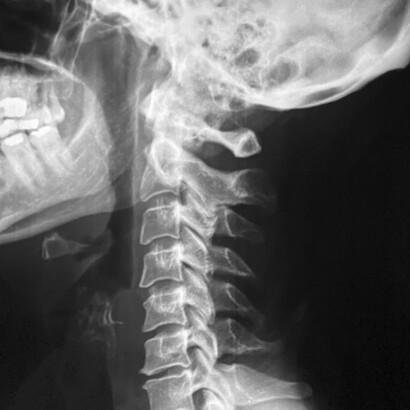

Las vértebras cervicales son 7 y están involucradas en la flexión, rotación, inclinación y extensión de la cabeza. Y lo hacen miles de veces al día, con lo que podemos hacernos una idea de que un simple desajuste puede desencadenar un bloqueo o dolor fácilmente.

El «decaimiento postural» es muy habitual en estos casos. Ya sabes, la típica postura en la que la cabeza y hombros caen hacia adelante con desgana. Una postura de ese tipo va debilitando nuestro sistema eléctrico de manera que cada vez es más sensible. Y el dolor aparecerá una y otra vez. Probablemente, tenemos una rectificación cervical. Es decir, esa parte de la columna ha perdido su forma natural y aparece recta, como si fuese una caña.

Artrosis cervical

Se trata de un proceso degenerativo en el que las articulaciones intervertebrales de las cervicales se van desgastando. Es frecuente a partir de los 45 años y afecta a cerca del 90% de la población mayor de 70 años.

La artrosis produce un adelgazamiento de los discos intervertebrales, así como de las articulaciones y cartílagos de la zona.

Este desgaste seca el hueso adyacente que empieza a rozarse y produce un tejido óseo llamado osteofito, que es una especie de protuberancia conocida como «pico de loro». Los osteofitos pueden comprimir un nervio, apareciendo el dolor.

Como el resto de los dolores de tipo mecánico, deben adoptarse medidas de higiene postural. La cervicoartrosis no siempre genera dolor, a veces tan solo se manifiesta con una limitación en los movimientos del cuello.